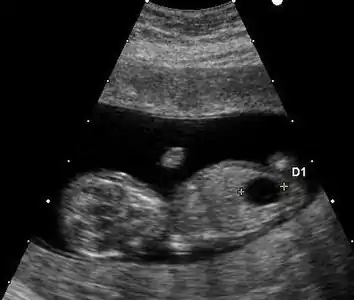

Ultrasound

Prenatal ultrasound can be used to screen for Down syndrome. Findings that indicate increased chances when seen at 14 to 24 weeks of gestation include a small or no nasal bone, large ventricles, nuchal fold thickness, and an abnormal right subclavian artery, among others.[99] The presence or absence of many markers is more accurate.[99] Increased fetal nuchal translucency (NT) indicates an increased possibility of Down syndrome picking up 75–80% of cases and being falsely positive in 6%.[100]

Ultrasound of fetus with Down syndrome showing a large bladder

Enlarged NT and absent nasal bone in a fetus at 11 weeks with Down syndrome